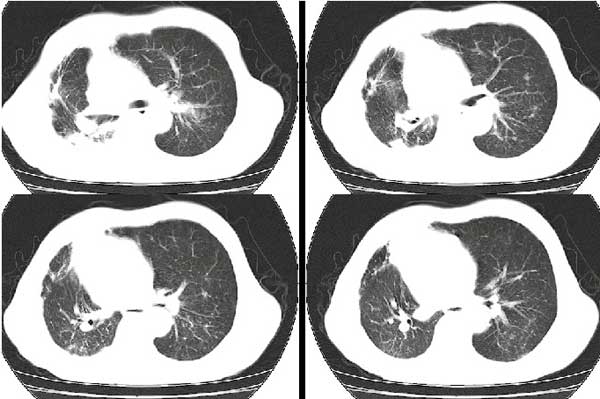

以下是引用扬仪在2005-5-12 20:46:40的发言:[br]右肺呈术后改变;双侧肺野散在分布斑片状、点状高密度病灶,(似可见“树芽征”);左上尖后段见斑团状高密度病灶(2个层面?),边缘毛糙,段性分布,与斜裂相邻,临近胸膜粘连;增强示病灶边缘强化,内呈水样密度;心影、纵隔右移,内可见4r淋巴结肿大。[br]意见:1、双肺继发性肺结核,左上为干酪病灶;[br] 2、矽肺合并感染;[br] 3、建议抗痨+抗炎。 [br]愚人之见,请高人指教!